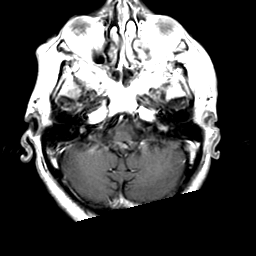

Meningioma, MR Study #2 -- Slice #3

[Home][Help][Clinical] Slice 3